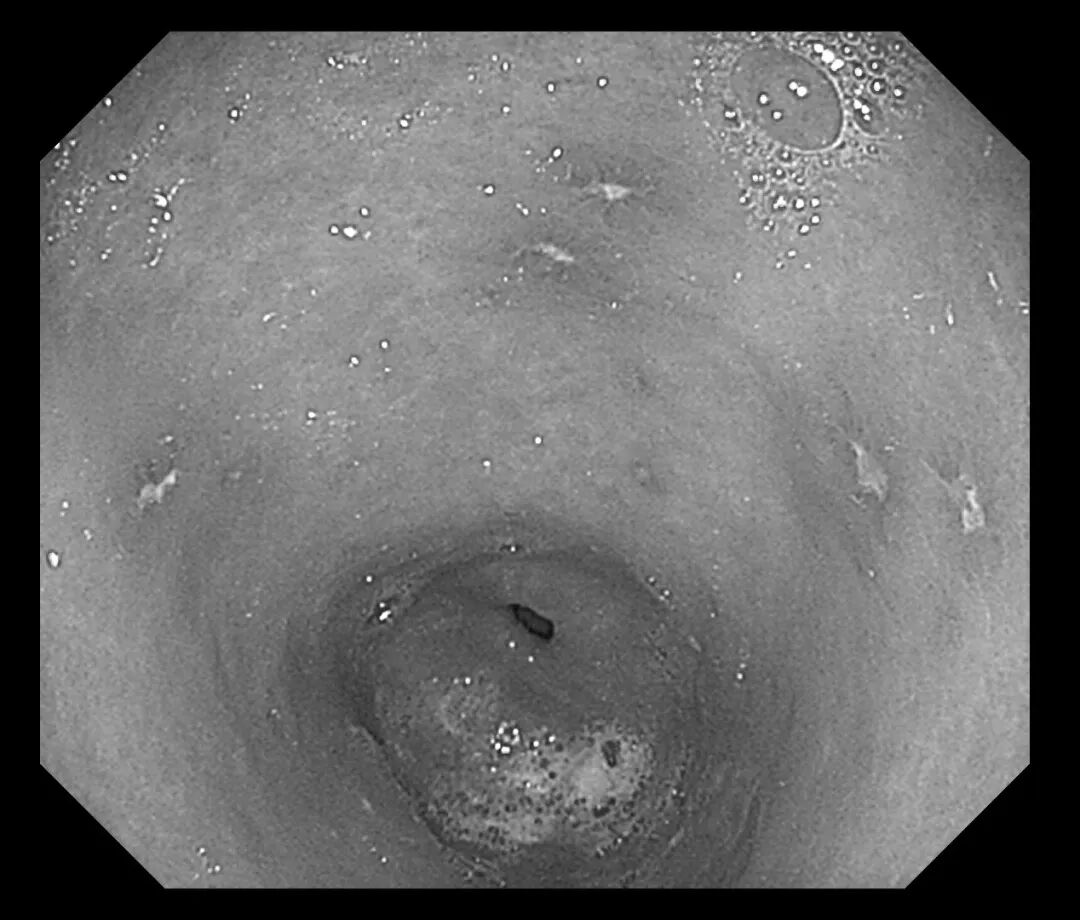

接诊医生刘润萍详细询问病史后,敏锐地意识到这可能是一例典型的“药物性胃溃疡”病例。为明确诊断,在评估患者情况后为其安排胃镜检查。检查结果令人大为震惊:胃窦、胃体等多处黏膜可见十余个直径0.3-0.5cm不等的溃疡灶,部分表面覆有白苔,周围黏膜充血水肿明显。结合患者近期用药史,考虑为“非甾体抗炎药相关性胃溃疡”。

(胃窦溃疡)